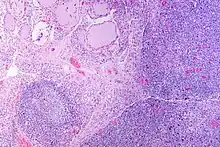

| The thyroid of someone with Hashimoto's thyroiditis as seen with a microscope at low magnification | |

Gross pathology of a thyroid with autoimmune thyroiditis may show an symmetrically enlarged thyroid.[22] It is often paler in color, in comparison to normal thyroid tissue which is reddish-brown.[22] Microscopic examination will show infiltration of lymphocytes and plasma cells. The lymphocytes are predominately T-lymphocytes with a representation of both CD4 positive and CD8 positive cells.[22] The plasma cells are polyclonal, with present germinal centers resembling the structure of a lymph node.[22] Fibrous tissue may be found throughout the affected thyroid as well.[22] Generally, pathological findings of the thyroid are related to the amount of existing thyroid function - the more infiltration and fibrosis, the less likely a patient will have normal thyroid function.[22] In late stages of the disease, the thyroid may be atrophic.[12]

Histologically, the hypersensitivity is seen as diffuse parenchymal infiltration by lymphocytes, particularly plasma B-cells, which can often be seen as secondary lymphoid follicles (germinal centers, not to be confused with the normally present colloid-filled follicles that constitute the thyroid). Atrophy of the colloid bodies is lined by Hürthle cells, cells with intensely eosinophilic, granular cytoplasm, a metaplasia from the normal cuboidal cells that constitute the lining of the thyroid follicles. Severe thyroid atrophy presents often with denser fibrotic bands of collagen that remains within the confines of the thyroid capsule.[52]

It is also characterized by invasion of the thyroid tissue by leukocytes, mainly T-lymphocytes. A rare but serious complication is thyroid lymphoma, generally the B-cell type, non-Hodgkin lymphoma.[53]